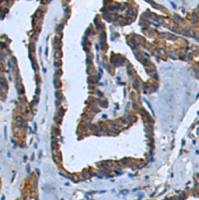

适用于: IP, WB, IHC-P

- IHC-P: Human breast carcinoma and cerebrum tissue; Mouse cerebrum and colon tissue; Rat cerebral cortex and colon tissue. WB: Recombinant human 0N4R Tau, 1N4R Tau and 2N4R Tau protein; Mouse hippocampus and brain lysate; Rat hippocampus lysate. IP: Rat hippocampus lysate